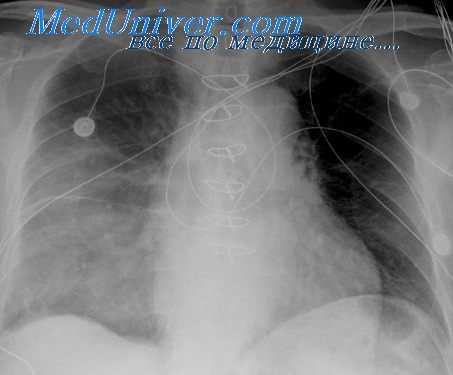

На рентгенограмме грудной клетки тимома имеет вид объемного образования неправильной формы, расположенного в переднем средостении. КТ грудной клетки значительно расширяет объем информации, полученный при первичной рентгендиагностике и в ряде случаев позволяет поставить морфологический диагноз. Уточнение локализации и взаимоотношения новообразования с соседними органами при КТ средостения позволяет в дальнейшем выполнить трансторакальную пункцию опухоли средостения, что чрезвычайно важно для гистологического подтверждения диагноза и верификации гистологического типа тимомы.